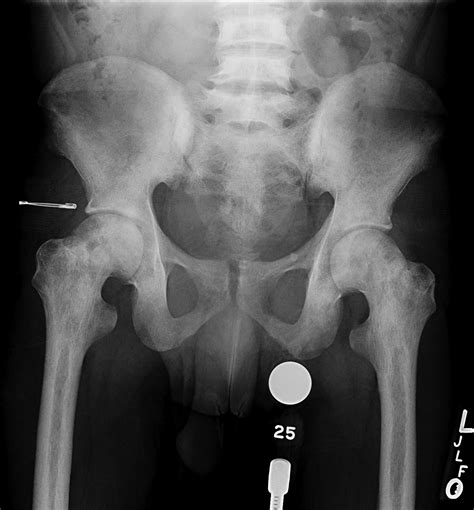

Phases of hip reconstruction recovery

Recovery after hip surgery is generally divided into several key phases, each with specific goals and milestones. Understanding what to expect during these periods helps manage expectations and reduces anxiety.